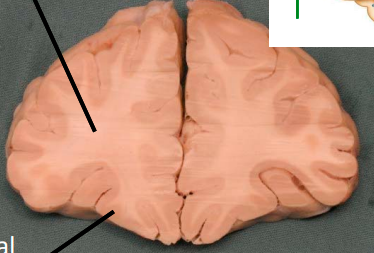

only portion of corona radiata seen right now are association fibers (which interconnect ipsilateral gyri) there are no internal capsule or lateral ventricles seen, indicating this cut is very rostral (pre-frontal cortex)

lable, note important features